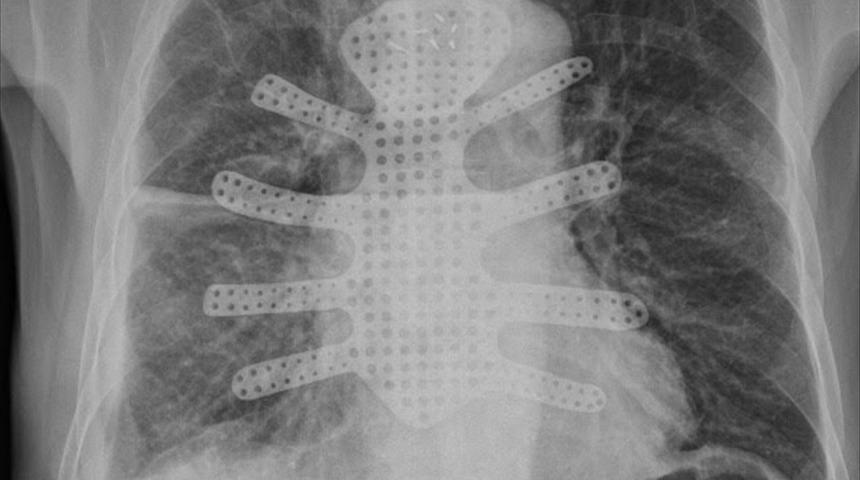

Göğüs Cerrahisi Kliniği Eğitim ve İdari Sorumlusu Prof. Dr. Onur Genç, Prof. Dr. Sedat Gürkök, Doç. Dr. Hasan Çaylak, Uzman Dr. Ersin Sapmaz yönetimindeki cerrahi ekip, ilk olarak Pelit'in göğüs kafesindeki 6 kilogramlık kitleyi ameliyatla çıkardı. Pelit'in göğüs kafesinde oluşan boşluk ise üç boyutlu yazıcıda titanyumdan üretilen "yapay göğüs kafesi" ile giderildi.

Operasyona ilişkin bilgi veren Göğüs Cerrahisi Kliniği İdari Sorumlusu Prof. Dr. Onur Genç, nefes darlığı ve göğüs ağrısı ile Tokat'tan gelen hastanın tomografisinde göğüs kafesinin büyük bir kısmını kaplayan, akciğerlerine de baskı yapan dev bir kitlenin tespit edildiğini aktararak, "Göğüs kafesinin bir kısmını, göğüs duvarının ön kısmını kitlenin tamamen kaplaması nedeniyle göğüs kafesinin de devamlılığını sağlamak amacıyla ince kesit tomografi bazlı tetkiklerini yaptırdık. METÜM merkezimizde titanyumdan göğüs kafesinin ön kısmını yeniden inşa ettirdik. Bu hazırlanan titanyum implantı da hastanın göğüs kafesine başarılı bir şekilde taktık. Hastamızın sağlığı gayet iyi durumdadır." diye konuştu.

METÜM Müdürü Doç. Dr. Simel Ayyıldız da "Solunum cihazına bağlı yaşamını sürdüren hastanın yaşamını devam ettirebilmesi için göğüs kafesinin üretimine başladık. Mühendisimiz Serdar Çınar ile bunun tasarımını gerçekleştirdik. METÜM olarak Göğüs Cerrahisi ve diğer branşlara da hizmet verebildiğimiz için mutluyuz." dedi. (AA)